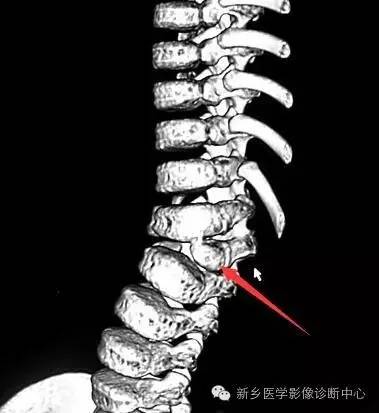

蝴蝶椎:椎体中央矢状位裂隙存在,椎体由两个尖端相对的楔形块构成,形状如蝴蝶。

脊椎椎体畸形(半椎体、蝴蝶椎)